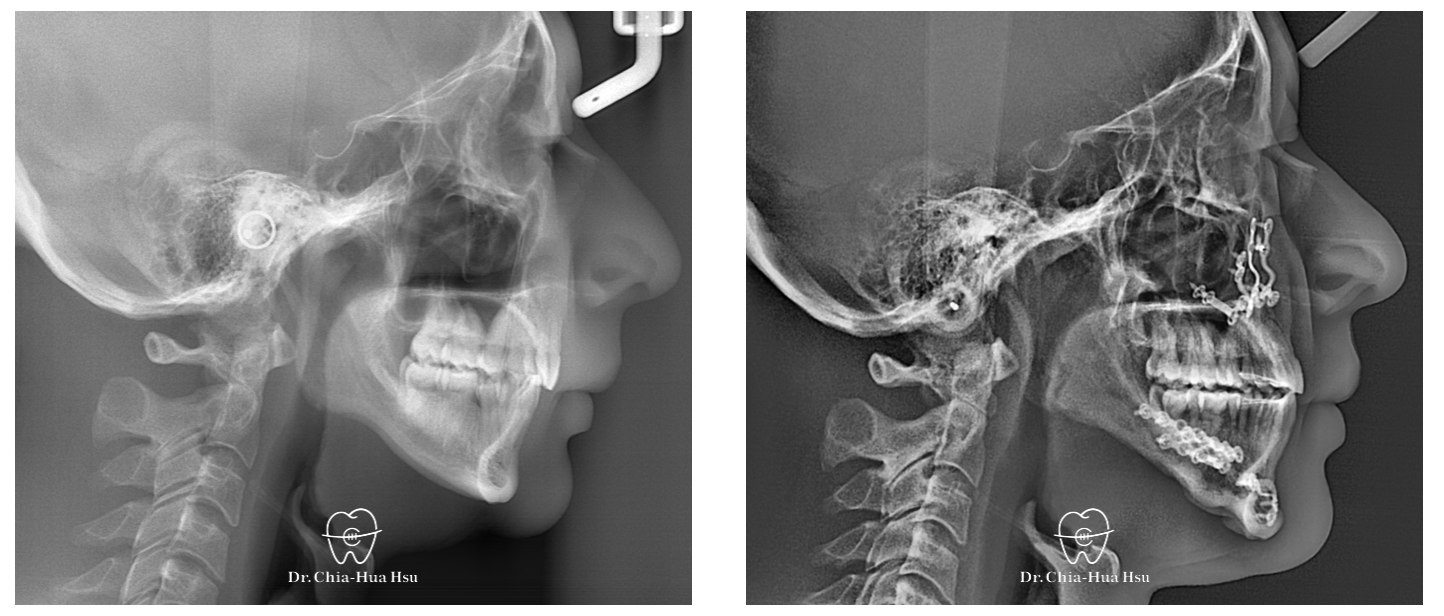

治療過程:患者有下顎後縮合併有睡眠呼吸中止症,接受了雙顎前移手術。

左圖為治療前之側顱X光攝影,右圖為手術後一天拍攝之側顱X光攝影,明顯可見其呼吸道狹窄獲得改善,患者術後睡眠品質亦大幅改善。